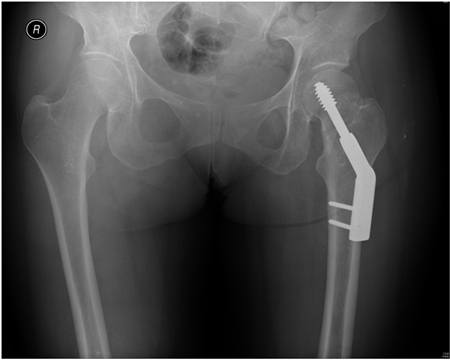

[Figure caption and citation for the preceding image starts]: Fractura intertrocantérica inestable en la radiografíaDe la colección de Bradley A. Petrisor, MSc, MD, FRCSC y de Mohit Bhandari, MD, MSc, FRCSC [Citation ends].